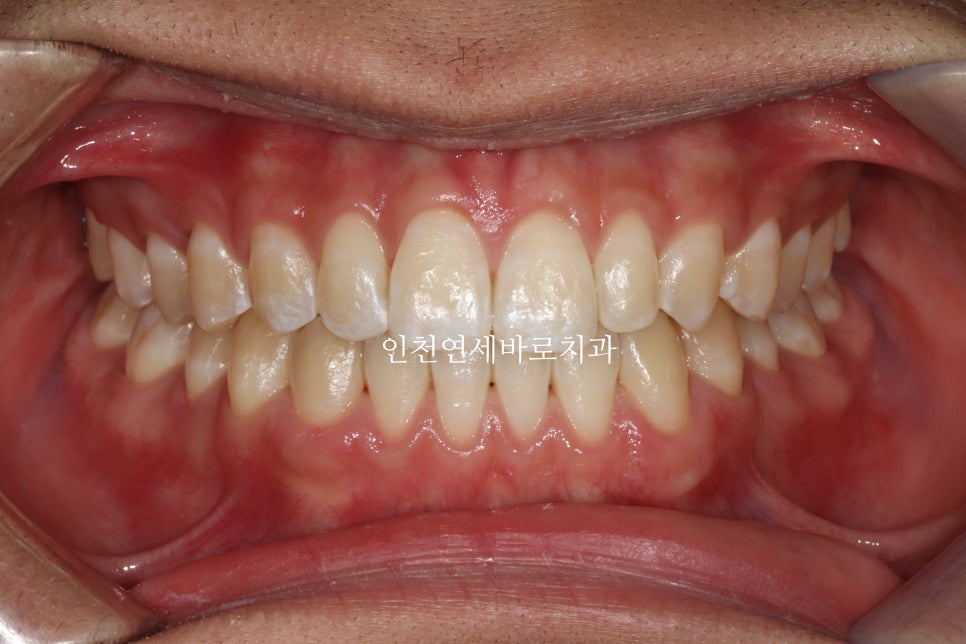

재제작 소요기간 한달을 포함해서 환자분이 병원에 오고 딱 1년만에 치료가 마무리 되었습니다.

문제가 되었던 오른쪽 어금니 교합도 좋게 마무리 하였습니다.

악궁확장장치는 사용하지 않았습니다.

이 증례의 경우 고1 남학생이 2020년 8월 24일부터 2021년 8월 13일까지 약 1년간 치료받았습니다. 한 번의 재제작 기간 1개월이 포함된 기간입니다.

- Patient: High school freshman with anterior spacing and crossbite issues

- Treatment period: August 24, 2020 – August 13, 2021 (1 year including one refinement)

- Treatment method: Invisalign without additional palatal expansion devices

- Successful correction of anterior spacing and posterior crossbite